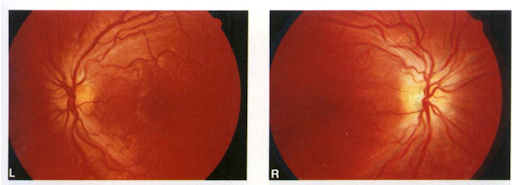

Other Neurologic and Ocular Manifestations: Symptoms may include blurry or hazy vision, color vision deficits, “snowfield vision”, or total blindness. Oddly, symptoms can often be asymmetric. Relevant exam findings that can be seen include a relative afferent pupillary defect when testing pupillary response, a central scotoma on visual field testing, and optic disc hyperemia, pallor, or papilledema on fundoscopic exam. It is very important to understand that this ocular damage is due to the toxicity of formic acid, the toxic metabolite of methanol, and not the parent compound itself.

Source: https://onlinelibrary.wiley.com/doi/pdf/10.1111/j.1442-9071.1992.tb00705.x

The mechanism by which methanol ingestion results in ocular toxicity is demonstrated in the below figure. Again, it is critically important to note that it is the formation of formic acid that ultimately results in visual deficits by the formic acid inhibiting cytochrome c of the electron transport chain in retinal pigmented epithelial and optic nerve cells. This results in impaired ATP production for energy use and ultimately damage to these cells that are critical for our vision.

On review of the patient case presented above, the patient may have subtly been showing signs of ocular toxicity. In the neurology resident exam, it was noted that he was not blinking to threat bilaterally, but was able to count fingers. This could represent findings of ocular toxicity.